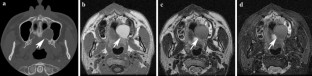

Non-contrast computed tomography and magnetic resonance imaging features of mucoepidermoid carcinoma in the salivary glands

Use of contrast-enhanced cross-sectional imaging is considered standard practice for investigating mucoepidermoid carcinoma (MEC) in the salivary glands. The purpose of this study was to present the common features of MEC on computed tomography (CT) and magnetic resonance imaging (MRI) without contrast enhancements, and to investigate the possibility of discriminating between MEC and pleomorphic adenoma based on the features observed on both modalities.

Twenty cases of biopsy-confirmed MEC originating in the salivary glands were reviewed and characterized by two oral and maxillofacial radiologists with regard to the following aspects: detectability, margin, border, encapsulation, content, contrast between lesion and masticator muscle, and bone changes.

Ninety percent of bone changes caused by MEC were detected by CT and sixty-nine percent of tumor existences were detected by MRI. The lesion border could provide a clue to distinguish MEC from pleomorphic adenoma.

Observation of MEC features was possible by both CT and MRI. Among the features, the lesion border could be a clue to distinguish MEC from pleomorphic adenoma.

Fig. 1